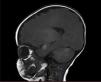

RNM de cerebro y columna total simple y contrastada: múltiples hiperintensidades cortico-subcorticales con compromiso temporal medial bilateral (epicentro en amígdalas y uncus), cortical parietal izquierda, tálamo derecho tanto posterior como anterior medial, algunos focos en la protuberancia y corteza cerebelosa bilateral (fig. 2). Lesiones en el tejido celular subcutáneo parietal derecho. Patrón de mielinización normal para la edad. Las imágenes de columna fueron normales.